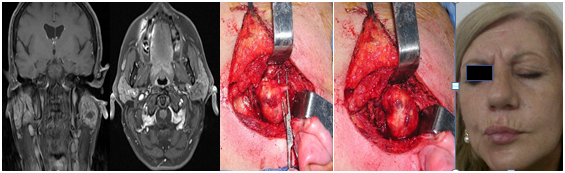

In three patients, a facial nerve monitor was used, and the incision was made in order to make the subcapsular dissection in an area that did not generate stimulation; in one, a mastoidectomy was performed to achieve a better expose of main facial nerve trunk, combined with the parotidotomy.

The function of the facial nerve was completely preserved in 2 patients (Brackmann I), another one had a slight dysfunction in the mandibular branch (Brackmann II: minimal asymmetry of movement in the mouth) and in another, nerve function was more affected (Brackmann III). The average period of control in this group was 4 years, and no recurrence was detected in the MRI (Figure 1–3).

Figure 1 Neurilemoma of the facial nerve at the parotid gland. Mastoidectomy, parotidotomy and intracapsular tumor resection

Figure 2 Schwannoma of the facial nerve at the parotid gland. Intracapsular resection with preservation of nerve function.

Figure 3 Total recovery of facial nerve function after intracapsular resection